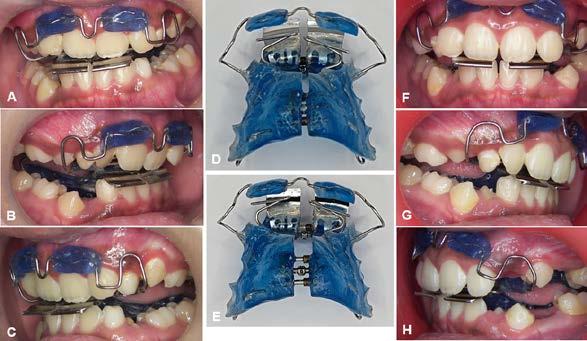

Figura 3. Primer aparto SN1 con almohadillas vestibulares. A. VF con aparato, B. VL derecha C. VL izquierda. D. SN1, vista oclusal (VO). Después de 7 meses del tratamiento se observa los avances obtenidos por el aparato y los ajustes del mismo los cuales observamos en las figuras: E. VO del SN1 7mm de crecimiento transversal, F. VF con aparato, 3G. VL derecha, H. VL izquierda.

Investigación clínica

Figura 4. Segundo Aparato SN1. A. VF con aparato, B. VL derecha, C. VL izquierda, 3D. SN1, VO. Después de 5 meses del tratamiento se observa los avances obtenidos por el aparato y los ajustes del mismo los cuales observamos en la imagen, E. VO del SN1 5 mm de crecimiento transversal, F. VF con aparato, G. VL derecha, H. VL izquierda.

Figura 5. Tercer aparato PIPS A. VF con aparato, B. VL derecha, C. VL izquierda, D. PIPS VO. Después de 7 meses del tratamiento se observa los avances obtenidos por el aparato y los ajustes del mismo los cuales observamos en la imagen, E. VO del PIPS sin los mantenedores de espacio, 5. VF con aparato, 5G. VL derecha, 5H. VL izquierda.

radiculares de O.D. 73 y 83 y rehabilitación oral completa de O.D. 54, 63,65 y 75. Se procedió a colocar aparatos ortopédicos para corrección de la maloclusión en enero del 2022.

El tratamiento inicio con AOF, SN1 con Equiplan adicionando almohadillas vestibulares en el maxilar para despresurizar la acción de la musculatura labial. La indicación de uso fue utilizarlo de forma continua solo retirándose para comer e higienizar, activar del tornillo tanto superior como inferior una vez a la semana, y se realizaron revisiones mensuales en la clínica para valorar avances, llevar

a cabo activaciones, ajustes del aparato e indicaciones. Como se observa en la Figura 3.

Al haber obtenido los avances programados en la corrección de la sobremordida vertical con esté AOF, se decide cambiar a un nuevo SN1, con equiplan sin almohadillas y con arco vestibular esto para continuar regularizando el plano de oclusión en el paciente, y fue utilizado por 5 meses de forma continua. Se mantuvieron las mismas indicaciones de uso, que en el aparato anterior. Como podemos observar en la Figura 4

El AOF Sn1 logró el avance mandibular, expansión programada, armonización de arcadas y regularización de la curva de Spee, entonces se determina cambiar dicho aparato por unas PIPS, clase I para mantener el espacio que corresponde a los O.D. 35 y 45, ya que fueron indicadas para extracción los O.D. 75 y 85, esperando la erupción de premolares para terminar el anclaje. Las indicaciones para el paciente fueron uso continuo de las PIPS por 3 meses, solo retirándose para comer e higienizar, revisiones mensuales en la clínica para activación y desgastes de los mantenedores de espacio, vigilando la erupción de los premolares. Posteriormente se indicó su uso nocturno por 4 meses más para mantener estabilidad de los resultados obtenidos.